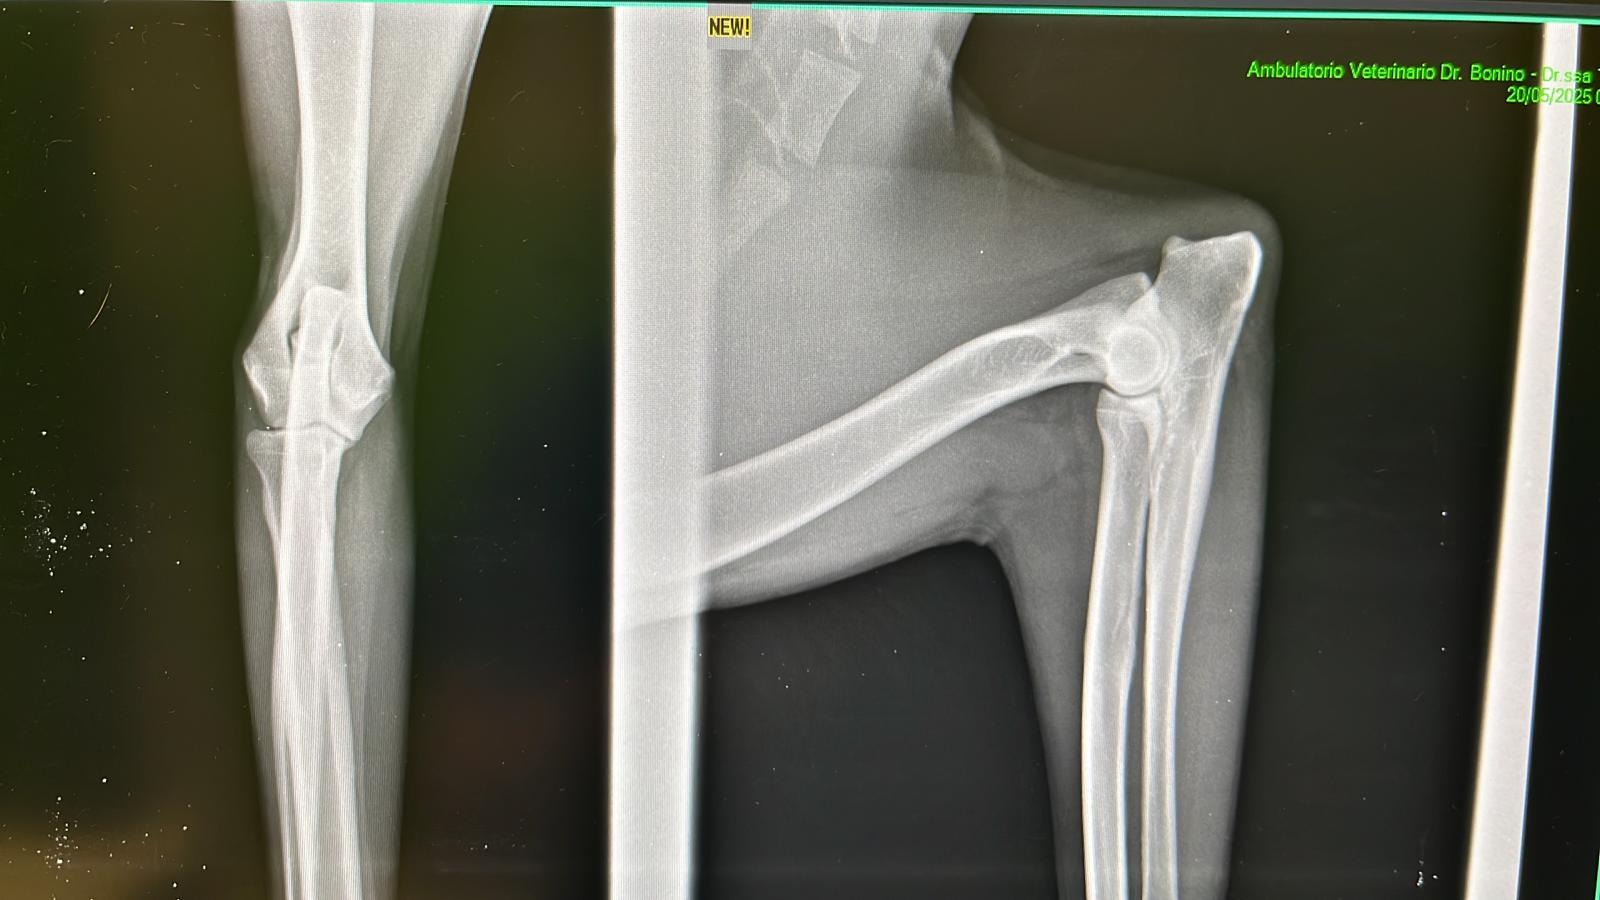

Purtroppo la mia situazione è un disastro: ho un brutto problema all'anca sinistra e alla regione sacroiliaca, non appoggio la zampa e non ho muscolo, la diastasi sacroiliaca non si sa se sia conseguente ad un investimento o a delle botte, ma sicuramente ha origine traumatica, sarà necessario effettuare una risonanza magnetica e una visita neurologica per capire se e come procedere per inserire una protesi nella mia anca che mi permetta di camminare e mi possa dare una vita "normale".